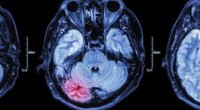

ΔΙΕΘΝΗΣ, ΠΟΛΥΚΕΝΤΡΙΚΗ, ΠΡΟΟΠΤΙΚΗ, ΝΟΣΟΚΟΜΕΙΑΚΗ ΜΕΛΕΤΗ, ΜΕ ΤΗ ΣΥΜΜΕΤΟΧΗ ΤΟΥ ΕΚΠΑ, ΓΙΑ ΤΗ ΣΥΣΧΕΤΙΣΗ ΤΗΣ ΛΟΙΜΩΞΗΣ ΜΕ SARS-CoV-2 ΜΕ ΑΓΓΕΙΑΚΑ ΕΓΚΕΦΑΛΙΚΑ ΝΟΣΗΜΑΤΑ

Έγινε αποδεκτή στο περιοδικό "Journal of Stroke & Cerebrovascular Diseases" μια πρωτότυπη εργασία που αφορά το πρωτόκολλο, της διεθνούς, πολυκεντρικής, προοπτικής, νοσοκομειακής μελέτης CASCADE, η οποία θα μελετήσει την αιτιοπαθογενετική συσχέτιση της λοίμωξης με SARS-CoV-2 με την επίπτωση και βαρύτητα των Αγγειακών Εγκεφαλικών Νοσημάτων που χρήζουν νοσοκομειακής νοσηλείας. Συγκεκριμένα, στη μελέτη αυτή θα συμμετάσχουν 52 κέντρα από 20 χώρες της Βόρειας Αμερικής (Η.Π.Α, Καναδάς), Νότιας Αμερικής (Αργεντινής), Ευρώπης (Ιταλία, Ισπανία, Ηνωμένο Βασίλειο, Γερμανία, Ελλάδα, Λουξεμβούργο), Ασίας (Κίνα, Ιαπωνία, Νότια Κορέα, Ιράν, Σιγκαπούρη, Μαλαισία, Ταϊλάνδη, Ινδία, Πακιστάν, Ηνωμένα Αραβικά Εμιράτα) και Ωκεανίας (Αυστραλία). Η μελέτη αυτή θα εκτιμήσει: α) τη συσχέτιση της νόσου COVID-19 με την επίπτωση και βαρύτητα Ισχαιμικών Αγγειακών Εγκεφαλικών Επεισοδίων, β) τη συσχέτιση της νόσου COVID-19 με την επίπτωση και βαρύτητα Αιμορραγικών Αγγειακών Εγκεφαλικών Επεισοδίων, γ) τη συσχέτιση της νόσου COVID-19 με την επίπτωση και βαρύτητα των Θρομβώσεων Φλεβωδών Κόλπων, δ) την επίδραση της νόσου COVID-19 στα νοσοκομειακά συστήματα υγείας και στις σύγχρονες θεραπείες των νοσηλευόμενων ασθενών με Αγγειακά Εγκεφαλικά Επεισόδια κατά το έτος 2020 και σε σύγκριση με τα προηγούμενα έτη 2018 & 2019 και το επόμενο έτος 2021. Η καταγραφή όλων των δεδομένων θα γίνεται με προκαθορισμένο και ομοιόμορφο τρόπο σε όλα τα συμμετέχοντα κέντρα με τη χρήση σταθμισμένων κλιμάκων εκτίμησης της βαρύτητας των Αγγειακών Εγκεφαλικών Επεισοδίων και την εφαρμογή διεθνών κριτηρίων αιτιοπαθογενετικής ταξινόμησης των Αγγειακών Εγκεφαλικών Επεισοδίων. Η μελέτη αυτή αποτελεί την μέχρι στιγμής μεγαλύτερη σε παγκόσμιο επίπεδο ερευνητική προσπάθεια μελέτης της επίδρασης της πανδημίας του COVID-19 στη νοσοκομειακή επίπτωση και αντιμετώπιση ασθενών με Αγγειακά Εγκεφαλικά Επεισόδια.